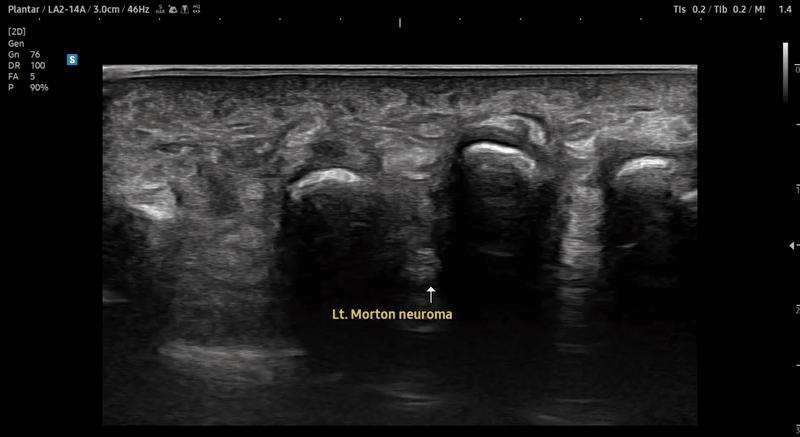

- 치료기간 : 2025. 7 . 4 ~ 2025 . 9 .1

- 치료횟수 : 10 회 (2cycle)

치료 전

치료 후